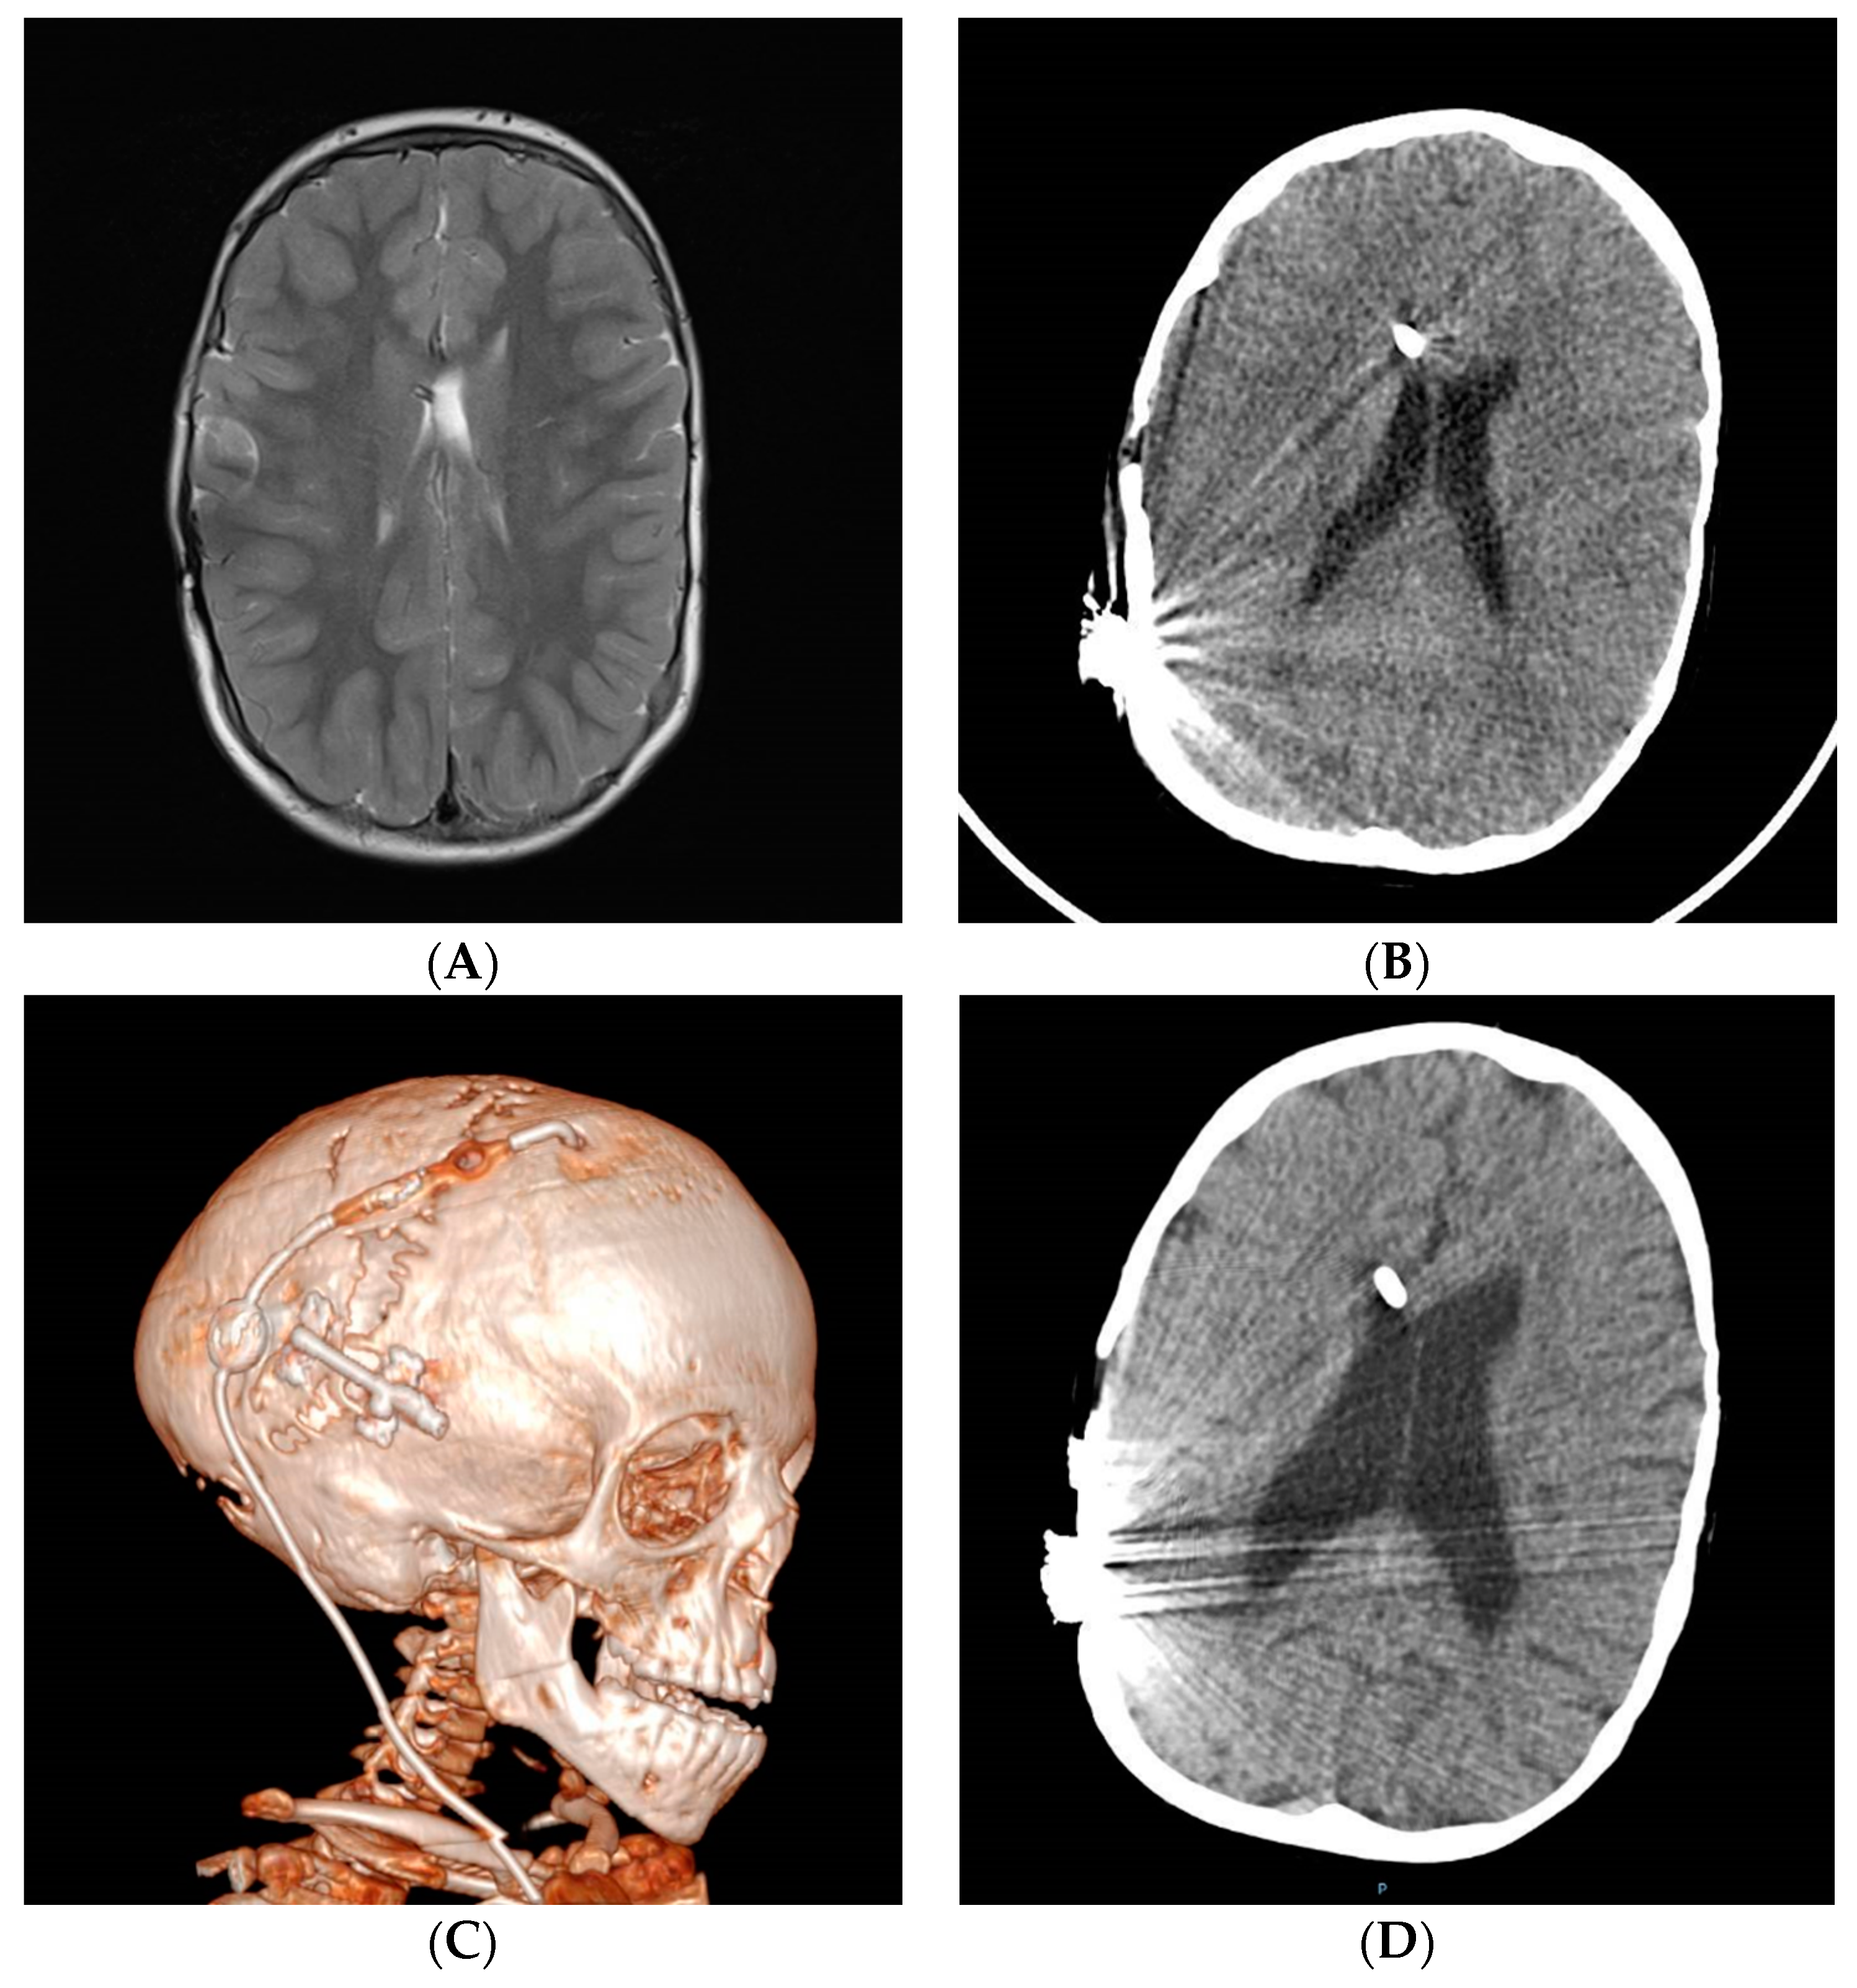

| Radiological findings | Small ventricles (moderate or normal sized also found). Extra-axial collections of fluid or blood. MRI: widened brain sulci, calcifications, etc. | Small ventricles with collapse onto the catheter tip. Occasionally with ventricular asymmetry, isolated compartments or IFV | Small ventricles. Suture sclerosis, laminated thickening, posterior fossa hypoplasia, etc. MRI: obliterated subarachnoid space, Chiari, spinal canal stenosis | Small ventricles with collapse onto the catheter tip. MRI: diffuse meningeal and arachnoid thickening, gadolinium hyperuptake, venous congestion, brain edema |